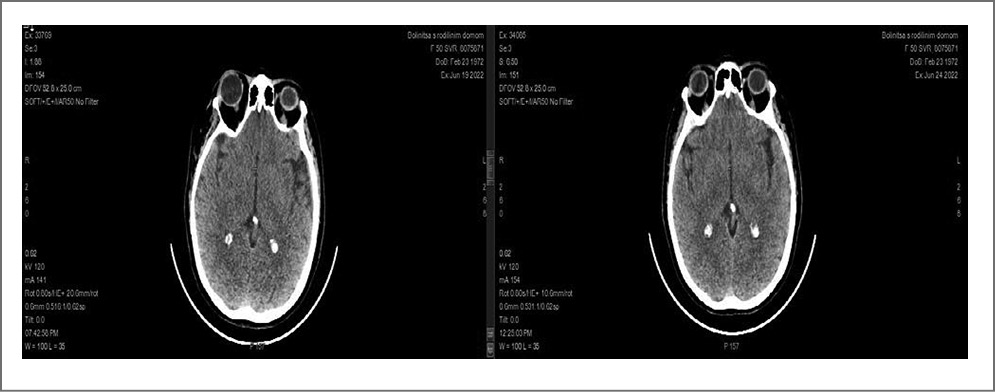

Пациентка П., 50 лет, доставлена в стационар через 3 ч 35 мин от начала заболевания. Развитие заболевания начиналось с появления слабости в левых конечностях, нарушения речи, асимметрии лица на фоне повышения АД до 180/90. Из хронических заболеваний у больной отмечалось наличие мочекаменной болезни с нефролитиазом левой почки и правого мочеточника. Острый обструктивный пиелонефрит справа. Чрескожная пункционная нефростомия справа под контролем ультразвукового исследования от 02.05.2022; хроническая железодефицитная анемия легкой степени тяжести; гипертоническая болезнь II стадии, 3-й степени, риск сердечно-сосудистых осложнений 3. Ревматоидный артрит. Ожирение 1-й степени (индекс массы тела 33,66). Инфаркт головного мозга в бассейне правой средней мозговой артерии от 1998 г. Постоянно принимает: гидроксихлорохин, клопидогрел, пропранолол, лозартан.

Уровень сознания: ясное. NIHSS (баллы): 7; ШКГ: 15; Индекс активности Ривермид (баллы): 7; Шкала Рэнкин: 3 балла; частота дыхательных движений: 20 в минуту; SPO2: 97%; АД 145/80 мм рт. ст.; частота сердечных сокращений: 60 уд/мин; лабораторные показатели в границах референсных значений.

По данным КТ головного мозга: КТ-картина очагов лейкоареоза сосудистого генеза в белом веществе головного мозга. Церебральный атеросклероз. Заместительная наружная гидроцефалия. Неполная аномалия Киммерли слева. Через 20 мин от поступления проведен консилиум и принято решение о назначении СТЛТ препаратом Фортелизин® в соответствии с инструкцией (10 мг, растворенные в 10 мл физраствора, внутривенно струйно в течение 10 с). При оценке через час отмечается регресс неврологического дефицита с 7 баллов до 3 баллов по шкале NIHSS.

При КТ-контроле головного мозга через сутки в веществе мозга не отмечается появление новых патологических очагов/участков гипо- и гиперденсивных. Срединные структуры не смещены. Дифференцировка вещества мозга сохранена. КТ-картина без отрицательной динамики (рис. 7).

Рис. 7. КТ головного мозга пациентки П.

При выписке оценка неврологического статуса по шкалам: NIHSS (баллы): 1; Индекс активности Ривермид (баллы): 8; Шкала Рэнкин: 2 балла.